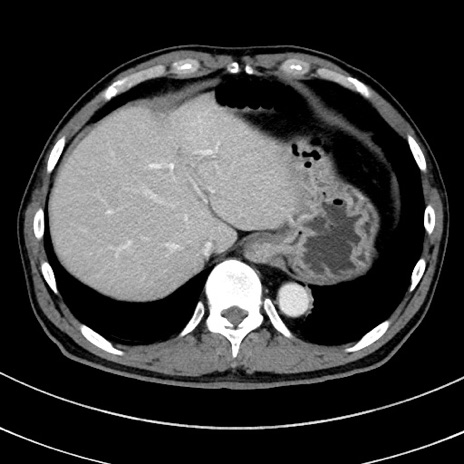

症例8(横断像)

【症例】 60歳代男性

【主訴】 黒色吐物

【現病歴】 4日前から嘔気自覚、2日前の朝食後にも嘔気あり、自分で手で嘔吐反射起こし嘔吐したところ血が混ざっていたため受診。

【既往歴】 5年前汎発性腹膜炎を伴う急性虫垂炎で手術、高血圧、前立腺肥大症、高脂血症

【身体所見】 腹部正中に手術癩痕あり 腹部平坦・軟圧痛なし膨満感あり

【データ】WBC 8400、CRP 4.54